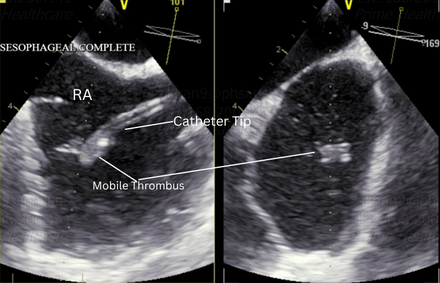

At follow-up, she remained emotionally distressed and convinced she had suffered a stroke. Repeat TTE raised concern for an intracardiac mass. A transesophageal echocardiogram (TEE) revealed a port-a-catheter tip in the right atrium with a large, mobile thrombus attached to its distal end. A small PFO with intermittent right-to-left shunting was also identified. The thrombus moved like a pendulum, intermittently striking the interatrial septum at the PFO. It is likely that embolization of a portion of the thrombus through the PFO led to a TIA. Interventional Radiology administered catheter-directed tPA to facilitate clot dissolution.

This case highlights a rare but clinically significant mechanism of paradoxical embolism originating from a central venous catheter, diagnosed through high clinical suspicion and confirmatory imaging.

In patients with neurologic symptoms and indwelling catheters, paradoxical embolism should be considered. TEE plays a vital role in detecting thrombi and intracardiac shunts. Early recognition and targeted therapy may prevent recurrence of embolic events.